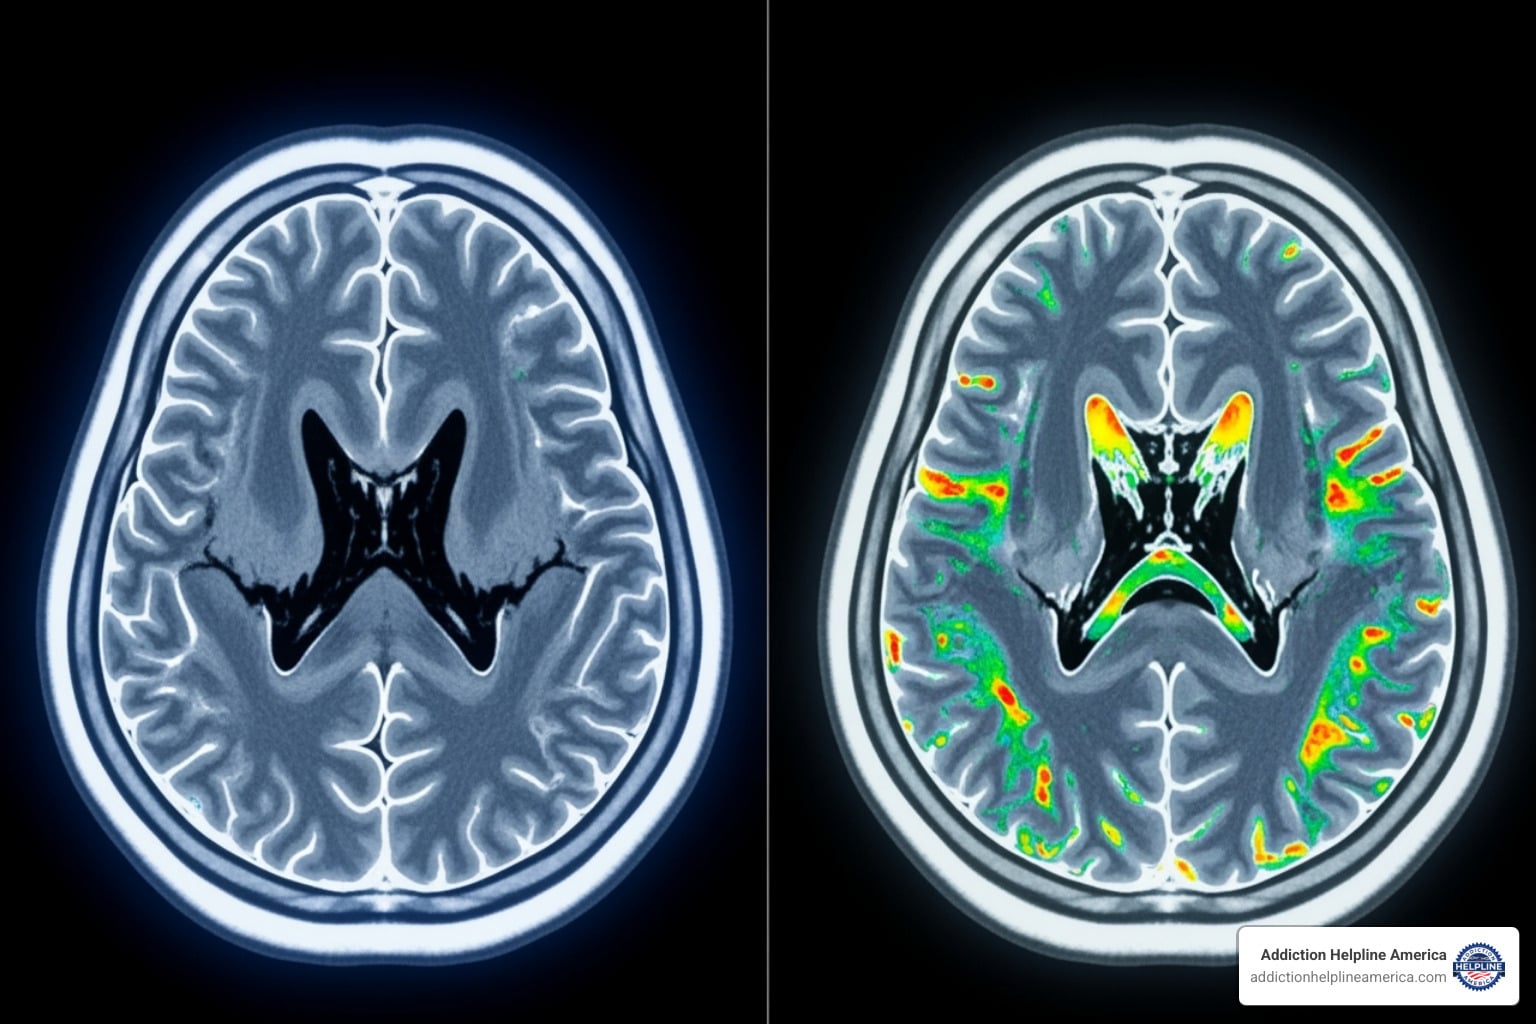

How Cocaine Addiction Affects the Brain

Here’s the truth: cocaine addiction isn’t a character flaw or a lack of willpower. It’s a brain disease. And understanding that changes everything.

When someone uses cocaine, it floods the brain with dopamine, the “feel-good” chemical. This creates an intense rush that the brain remembers and craves. Over time, chronic use rewires the brain:

1. The natural reward system gets dulled: Everyday pleasures feel flat without the drug.

2. The stress response goes into overdrive: Anxiety and irritability become constant when not using.

3. Powerful triggers are created: Cues like people, places, or times of day can spark intense cravings.

illustrating the contrast between a healthy brain scan and one affected by chronic cocaine use - Cocaine Addiction Treatment